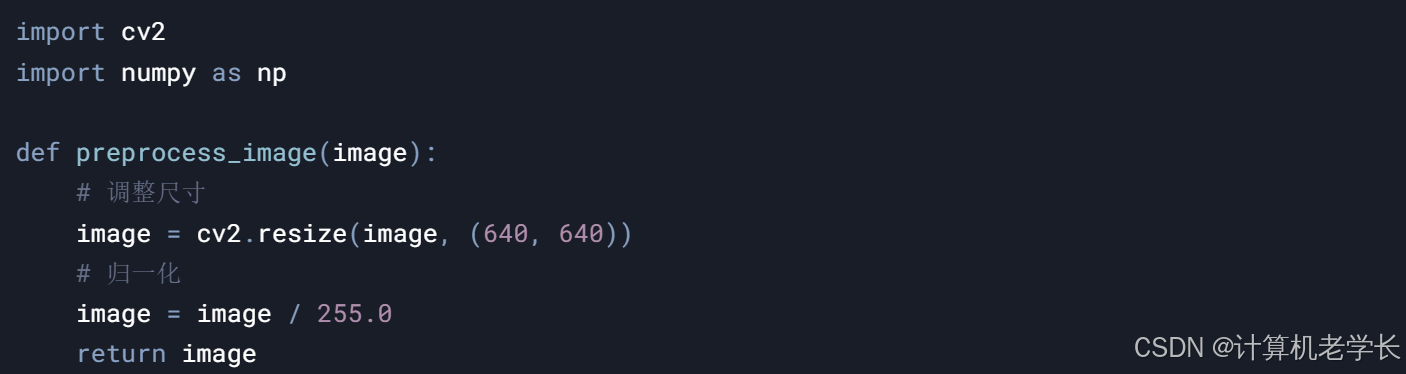

3.2.3 数据预处理模块

图像标准化

统一尺寸

-

4.2 数据预处理